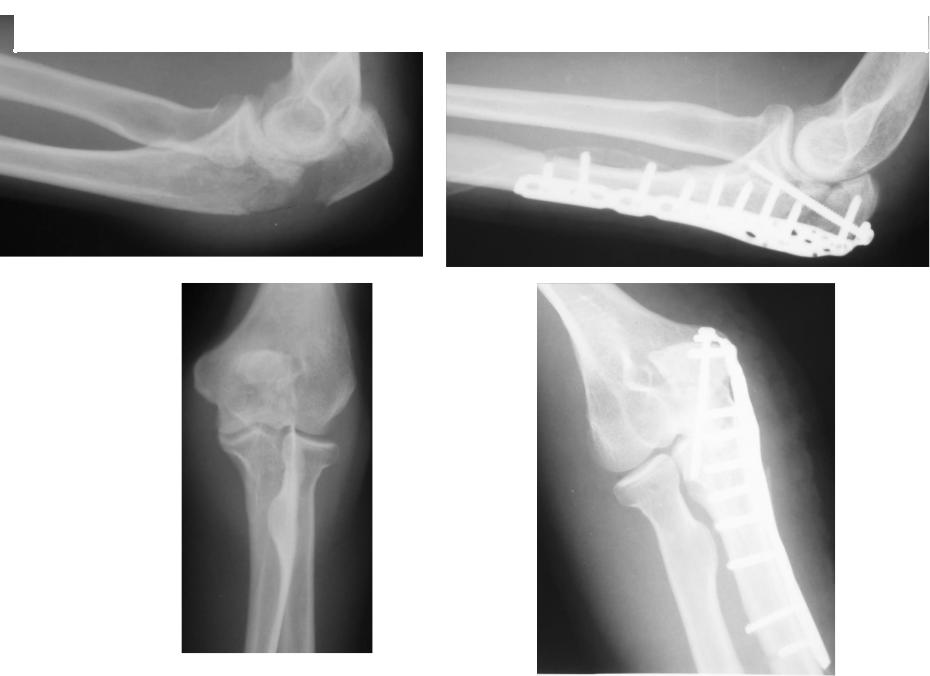

Клинический пример 3

Через 12 месяцев